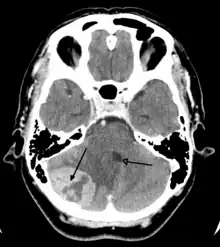

A posterior fossa tumor leading to mass effect and midline shift

Although there is no specific or singular symptom or sign, the presence of a combination of symptoms and the lack of corresponding indications of other causes can be an indicator for investigation towards the possibility of a brain tumor. Brain tumors have similar characteristics and obstacles when it comes to diagnosis and therapy with tumors located elsewhere in the body. However, they create specific issues that follow closely to the properties of the organ they are in.[39]

CT scan of a brain tumor, with its diameters marked as an X. There is hypoattenuating (dark) peritumoral edema in the surrounding white matter, with a "finger-like" spread.

Medical imaging plays a central role in the diagnosis of brain tumors. Early imaging methods – invasive and sometimes dangerous – such as pneumoencephalography and cerebral angiography have been abandoned in favor of non-invasive, high-resolution techniques, especially magnetic resonance imaging (MRI) and computed tomography (CT) scans,[38] though MRI is typically the reference standard used.[41] Neoplasms will often show as differently colored masses (also referred to as processes) in CT or MRI results.